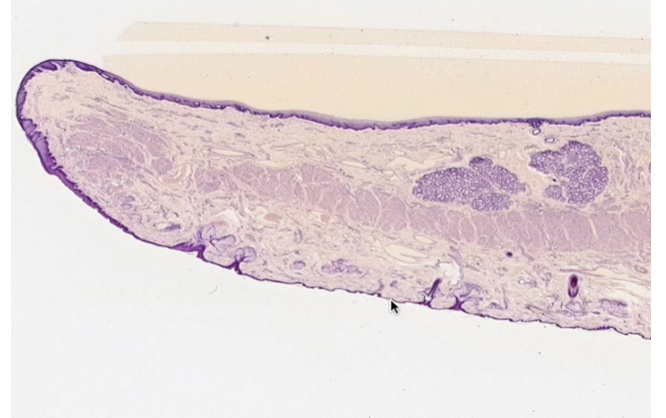

ID this tissue

Tongue